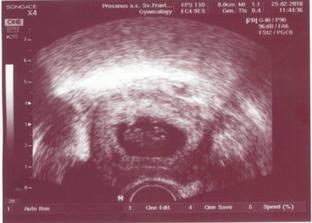

# 25.2. o 10.00 - druhá návšteva prebehla rýchlo. Ocko s nami tentokrát nemohol ísť, čo je škoda. Ale aspoň som sa mala na čo vyhovárať, keď som si pýtala fotku 🙂 Malý valibuk od poslednej návštevy riadne podrástol - už máme 2cm! Mám obrovskú radosť- a hormóniky riadne pracujú... Kým pani doktorka zapisovala do PC, nemohla som sa jej na nič spýtať, lebo sa mi slzy tlačili do očí. O fotke ani nehovorím, tú som si riadne prezrela až po pol hodinke, keď ma to dojatie ako-tak prešlo.